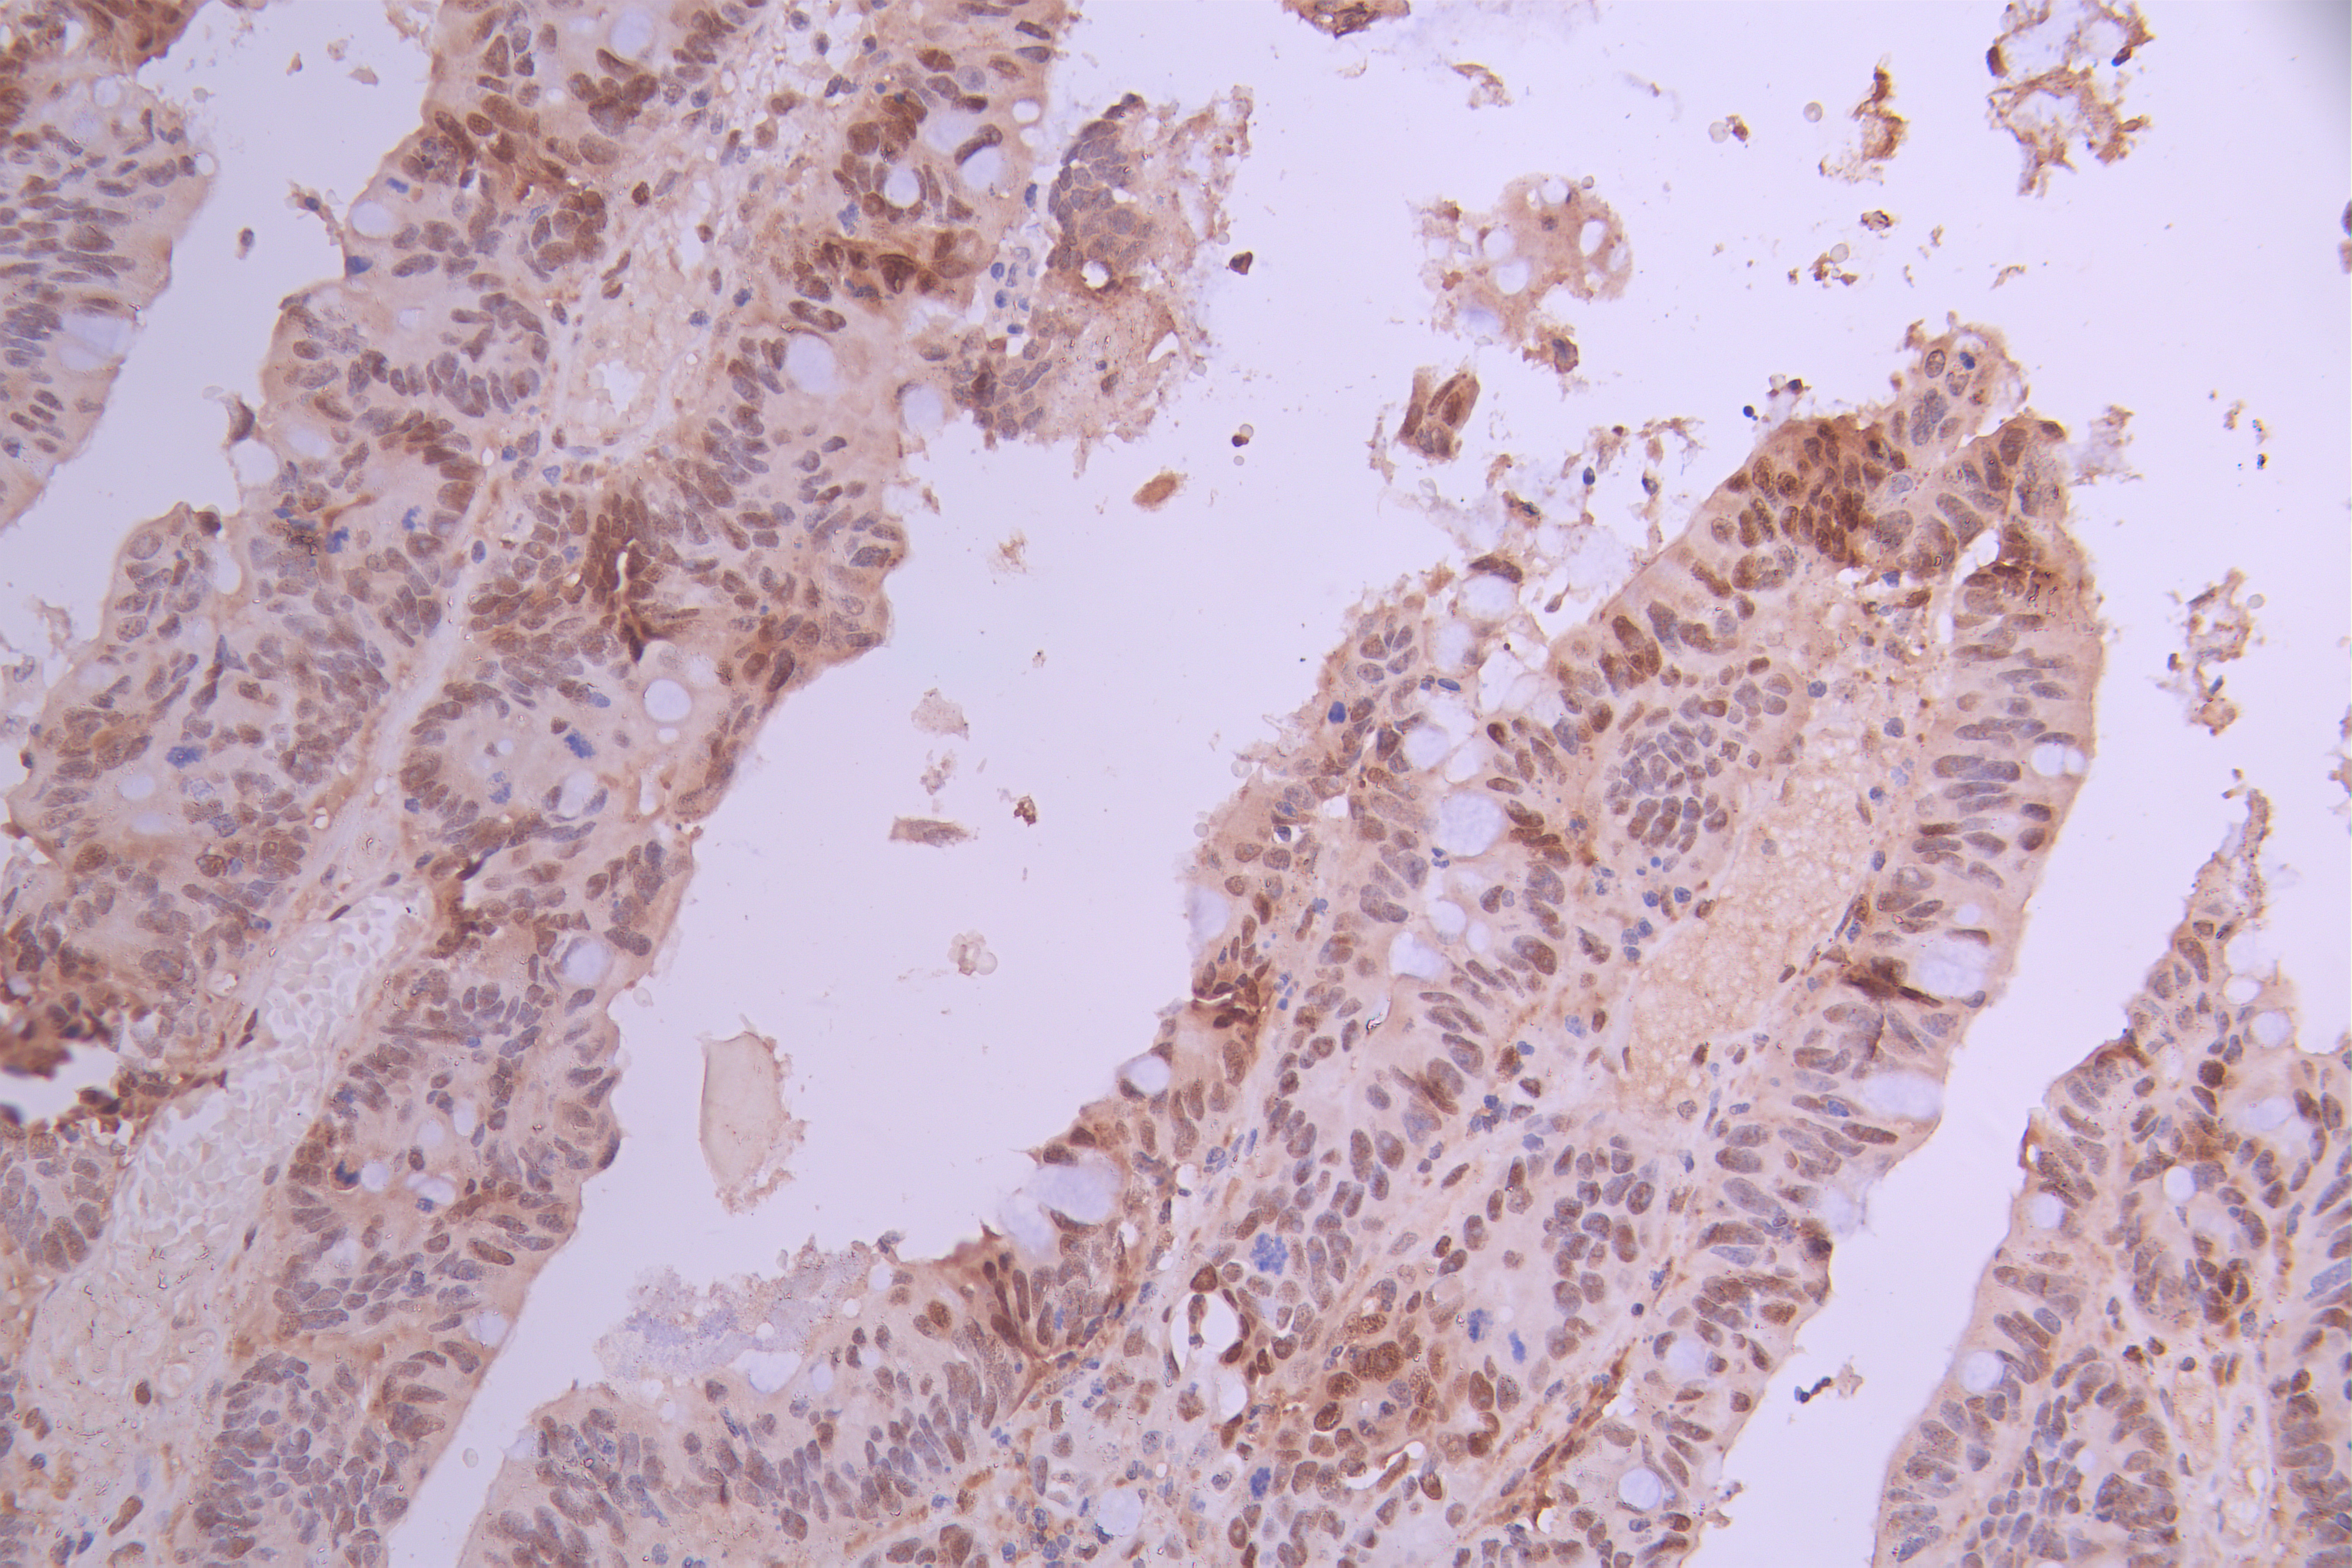

• IHC image of CSB-RA276081A0HU diluted at 1:100 and staining in paraffin-embedded human colorectal cancer performed on a Leica BondTM system. After dewaxing and hydration, antigen retrieval was mediated by high pressure in a citrate buffer (pH 6.0). Section was blocked with 10% normal goat serum 30min at RT. Then primary antibody (1% BSA) was incubated at 4°C overnight. The primary is detected by a Goat anti-rabbit polymer IgG labeled by HRP and visualized using 0.05% DAB.